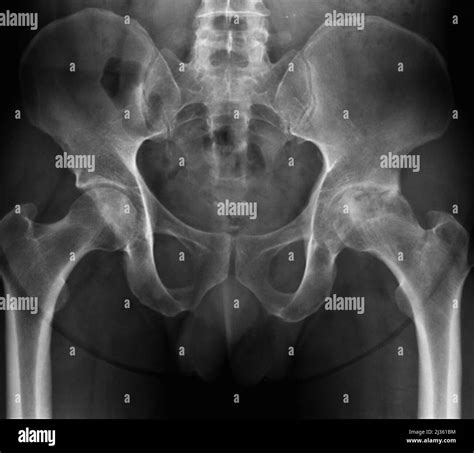

So, to really get a handle on bone rubbing on bone , we need to understand what osteoarthritis actually is. At its core, osteoarthritis (OA) is a degenerative joint disease. This means it’s a condition where the protective cartilage that cushions the ends of your bones within a joint gradually wears down over time. Think of cartilage as the slick, rubbery material that covers the ends of bones where they meet to form a joint. Its job is super important: it allows bones to glide smoothly over each other, absorbing shock and preventing friction. In a healthy joint, this cartilage is smooth, flexible, and abundant. But with OA, this cartilage starts to break down. It can become rough, frayed, and thin, and in severe cases, it can wear away completely. When that happens, you’re left with direct contact between the bones themselves. This is the ‘bone rubbing on bone’ sensation that causes so much pain and discomfort. It’s not just the bones, though. As the cartilage deteriorates, other changes happen within the joint. Bone spurs, which are extra bits of bone, can develop along the edges of the bones. The tissues lining the joint, called the synovium, can become inflamed. The ligaments and tendons surrounding the joint can also be affected, leading to instability and weakness. All these factors contribute to the hallmark symptoms of OA: pain, stiffness, swelling, and a decreased ability to move the joint. It’s a complex process, and while ‘wear and tear’ is a common way to describe it, it’s more than just simple overuse. It involves a combination of mechanical stress and biological processes that lead to the breakdown of joint tissues. The result is a joint that doesn’t function as it should, making everyday activities feel like a monumental effort. We’re talking about everything from walking and climbing stairs to simply gripping an object or turning a doorknob. The impact on quality of life can be profound, which is why understanding the condition and its mechanisms, like that painful bone rubbing on bone friction, is so critical for finding effective management strategies.

Alright, let’s talk about the million-dollar question: why does the cartilage wear away , leading to that dreaded bone rubbing on bone situation in osteoarthritis? It’s not like your cartilage just decides to quit one day. It’s usually a combination of factors, and it’s important to remember that it’s not just about age, although age is a big one. Genetics play a significant role; if your parents or grandparents had OA, you might be more predisposed to it. This isn’t about blaming your DNA, but understanding that some people are simply born with a genetic makeup that makes their cartilage more susceptible to breakdown. Then there’s the biomechanics – how your joints move and the forces they endure. If you have joint misalignment, like knock-knees or bowlegs, or if you’ve had a previous joint injury (think ACL tears or meniscus damage from sports), those joints are under abnormal stress. This uneven pressure can accelerate cartilage wear. Overuse and repetitive stress are also major culprits. Think about athletes, construction workers, or anyone whose job or hobby involves constantly stressing the same joints. While exercise is generally good, extreme or repetitive high-impact activities without adequate rest and recovery can wear down cartilage over time . Obesity is another massive factor, especially for weight-bearing joints like the knees and hips. Carrying extra weight means your joints have to work much harder and bear significantly more load with every step. This extra pressure puts immense strain on the cartilage, leading to faster deterioration. Believe it or not, even metabolic factors and certain medical conditions can contribute. Diabetes, for instance, has been linked to an increased risk of OA. And then there are inflammatory conditions like rheumatoid arthritis, which, while different from OA, can damage cartilage and increase the risk of developing secondary osteoarthritis. So, it’s a complex interplay of genetics, injury history, mechanical forces, lifestyle, and overall health that contributes to the breakdown of that crucial cartilage. Without it, you’re left with the painful reality of bone rubbing on bone , and understanding these causes helps us figure out how to prevent, slow down, or manage the condition.

Spotting the early signs of osteoarthritis is key, especially before you get to the severe bone rubbing on bone stage. The symptoms often develop gradually, so you might dismiss them at first. But knowing what to look for can help you seek help sooner and manage the condition more effectively. The most common and telling symptom is joint pain . This pain typically worsens with activity and improves with rest. It might start as a dull ache or a burning sensation in the joint. As the condition progresses and the cartilage wears thin, the pain can become more constant and severe, especially during or after movement. You might feel it when you first wake up, or after sitting for a long time – that’s often called ‘start-up stiffness’. Another hallmark symptom is stiffness . This is particularly noticeable in the morning or after periods of inactivity. You might feel like your joints are ‘stuck’ or difficult to move. This stiffness usually lasts for less than 30 minutes, which helps distinguish it from inflammatory types of arthritis. As the cartilage wears away and bone spurs form, you might also experience loss of flexibility . It becomes harder to move your joint through its full range of motion. Bending your knee or straightening your finger might become a challenge. Some people also report feeling a grating sensation or hearing a cracking sound (crepitus) when they move the affected joint. This is often a direct result of the rough surfaces of the bones and bone spurs rubbing together – that audible confirmation of the bone rubbing on bone phenomenon. Swelling can also occur, especially after increased joint use. The joint might look puffy or feel warm to the touch due to inflammation. In later stages, you might notice tenderness when you press on the joint, and some people even develop bone spurs that can feel like hard lumps around the joint, particularly in the finger joints. If you’re experiencing persistent joint pain, stiffness, or any of these other symptoms, especially in your knees, hips, hands, or spine, it’s definitely worth talking to a doctor. Early diagnosis and management can make a huge difference in slowing progression and maintaining your quality of life, long before the bone rubbing on bone becomes unbearable.